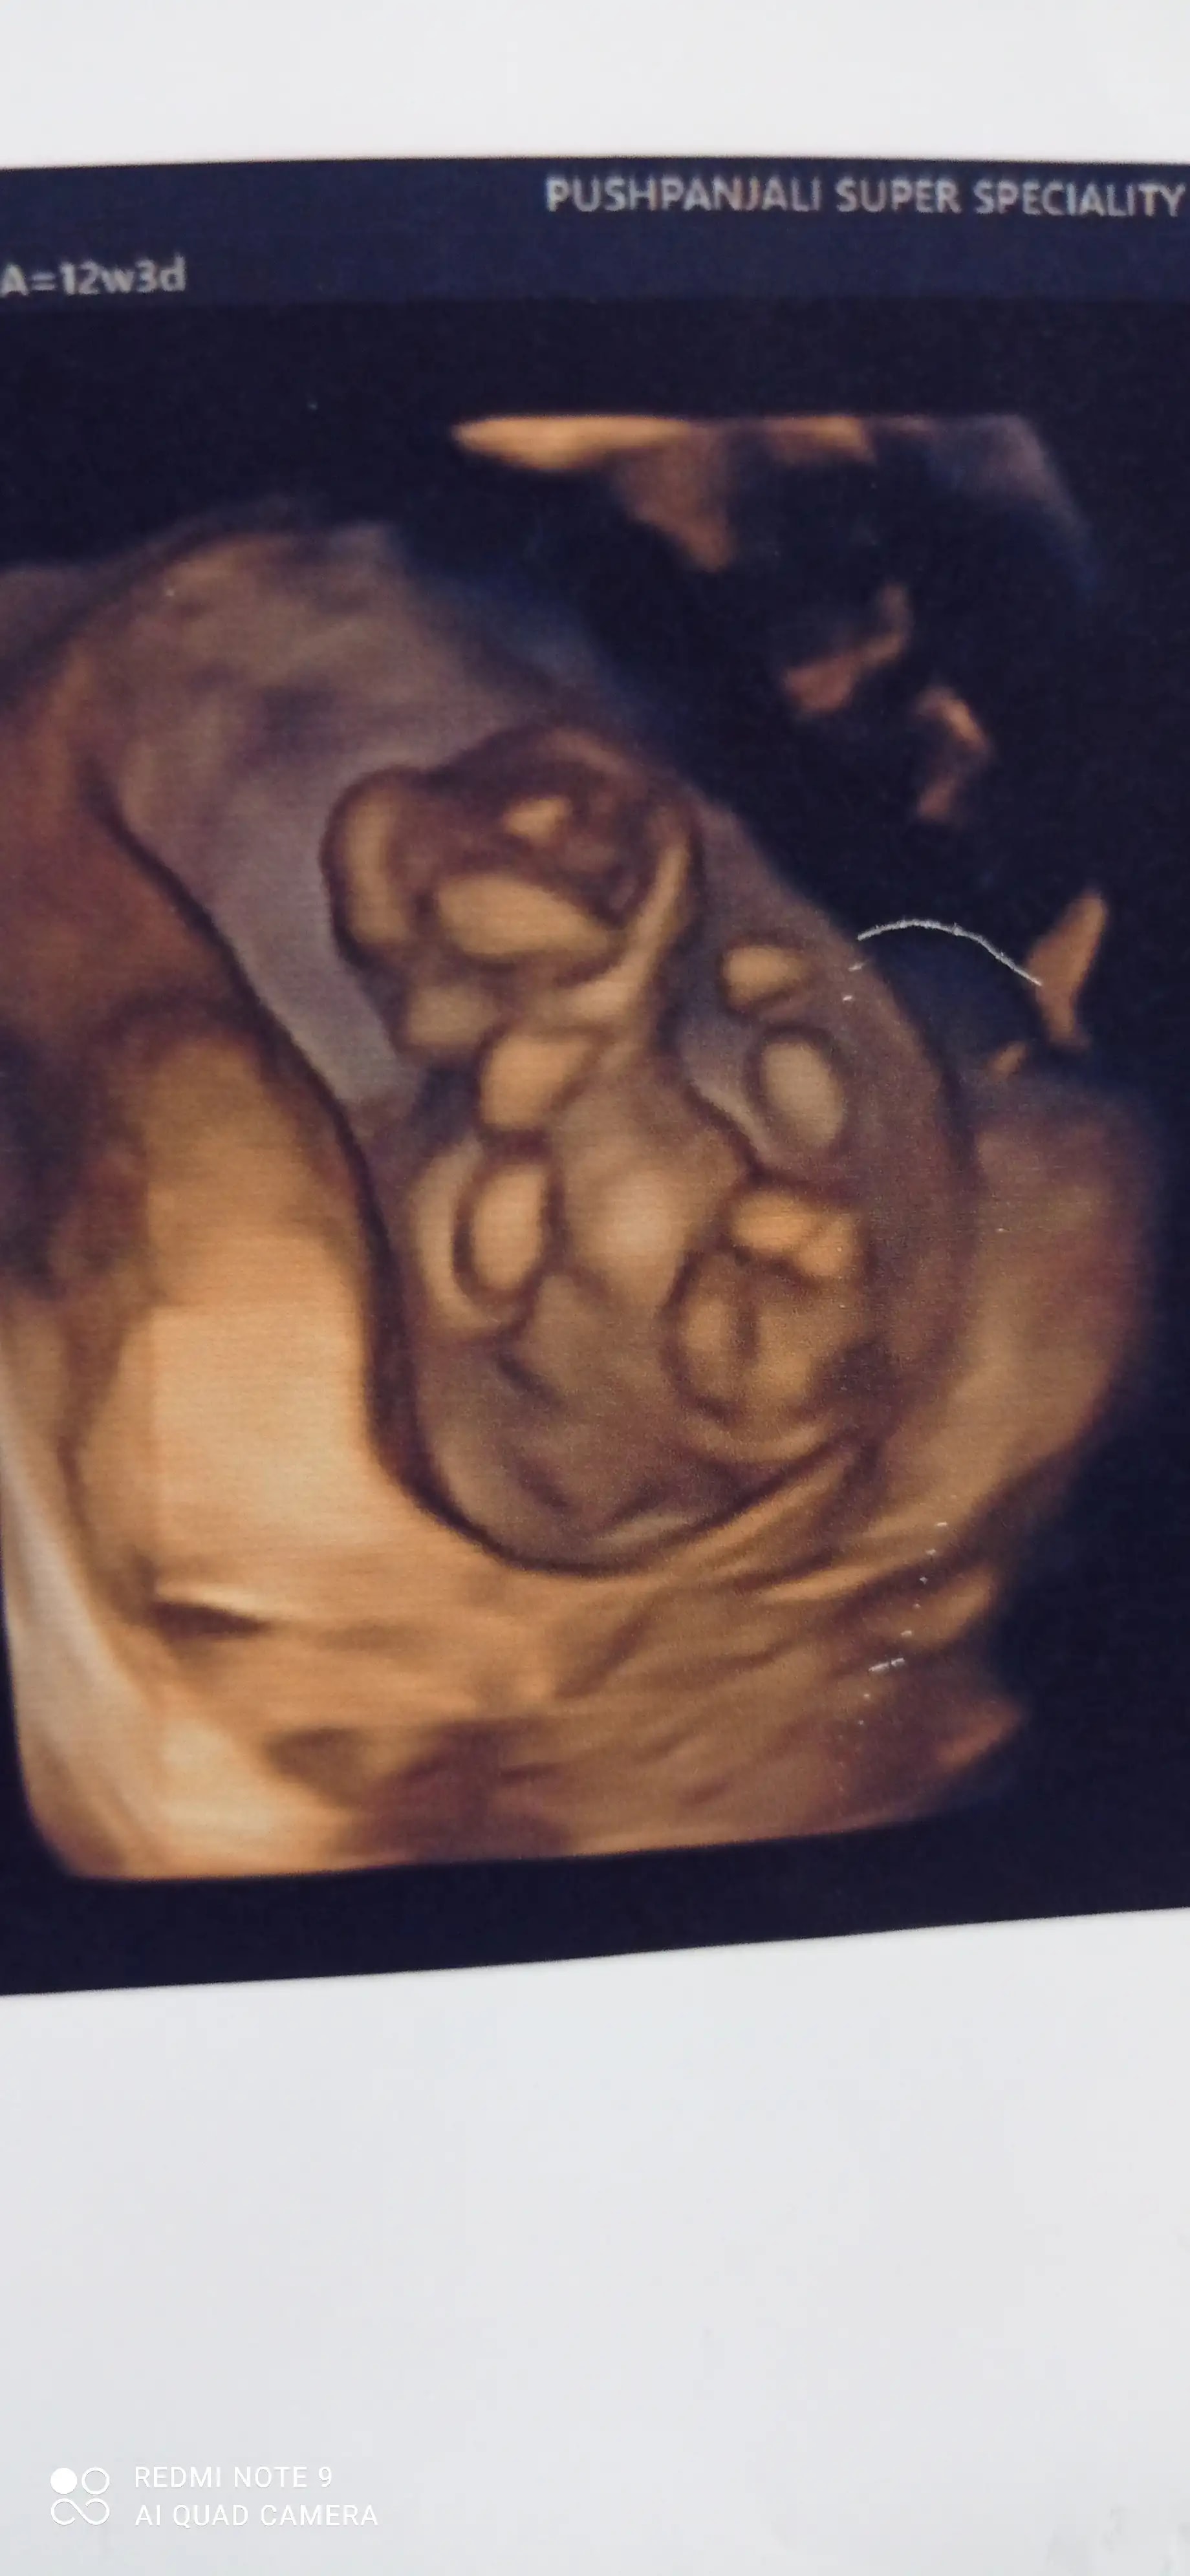

Q: Plz koi batao yeh kya h

A: Baby ho skta h ye report to 12 week ki h ... See more